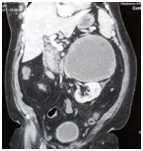

A 59-year-old man weighting 102kg, presented with vague abdominal discomfort in the left side of abdomen of 14years duration. He described it as, on and off in nature. Other constitutional symptoms were, less than 10% weight loss noted. He is Type 2DM. No significant past surgical history. His abdominal physical exam was normal. On laboratory tests, evaluation for pheochromocytoma was done and all parameters were b within normal limits. Computed Tomorgraphic Scan with non-ionic contrast showed a solid well-differentiated heterogeneous mass, 17 cm×15cm×12 cm, located between the left kidney, spleen and aorta (Figure 1).

Figure 1 Computed Tomorgraphic Scan with non-ionic contrast showed a solid well-differentiated heterogeneous mass, 17cm×15cm×12cm, located between the left kidney, spleen and aorta.